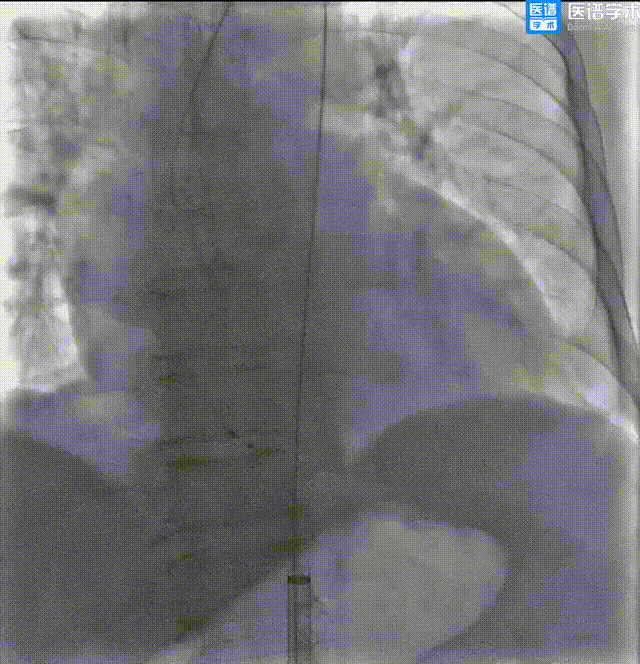

导丝跨瓣

瓣膜过弓、跨瓣

瓣膜定位